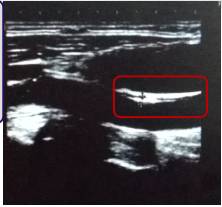

5、外周血管彩超

方框中为右侧颈总动脉

左侧颈总动脉

方框中为右侧颈内动脉起始部

●右侧颈总动脉中段前壁可见约16×2.0mm的强回声斑块。

●右侧颈内动脉起始部后壁可见约2.5×0.9mm的点状强回声。

●左侧颈总动脉中段前壁可见约17×1.7mm的不均质低回声斑块,近分叉处前壁、内侧壁、后壁可见偏心性不均质低回声斑块,致颈总动脉分叉处狭窄,直径狭窄率约50%。

●双侧颈总、颈内、颈外动脉粥样硬化斑块形成。

●左侧颈总动脉局部轻-中度狭窄。

●双侧髂、股、腘动脉粥样硬化斑点形成,双侧髂、股、腘静脉瓣无异常。